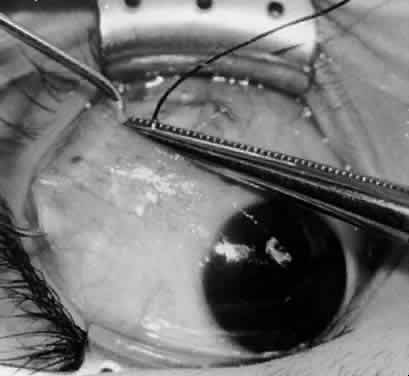

Fig. 14. The inferior temporal vortex vein, 8 mm posterior to the temporal insertion of the inferior rectus muscle, is held on a Green muscle hook.

Fig. 15. The placement of sutures within the sclera for a recession procedure of 10 mm. The anterior suture is placed 3 mm temporal and 2 mm posterior to the lateral insertion of the inferior rectus muscle, and the posterior suture is placed 3 mm further posteriorly.

Fig. 16. Two sutures straddle the inferior temporal vortex vein insertion for a 14-mm recession procedure.

Fig. 17. Knots are tied to show the placement. The inferior oblique muscle is held on a Stevens muscle hook.

Fig. 18. The final position, with the inferior oblique muscle recessed 10 mm. The inferior rectus muscle is retracted with a Green muscle hook. As described in the text, the 14-mm recession would place the inferior oblique muscle over the inferior temporal vortex vein, and the 6-mm recession would place the inferior oblique muscle anterior and nasal to this position.

Fig. 19. A 14-mm inferior oblique muscle recession is placed over the inferior temporal vortex vein.

Fig. 20. Optional closure of the incision with a 6-0 Vicryl suture. The incision may be allowed to heal without a suture.